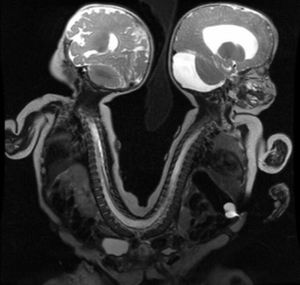

A very special MRI showing the case of a rare set of conjoined twins that were successfully separated on August 29, 2011. The orthopaedic team was performing the 13-hour surgery. The twins were joined back to back at the pelvis and lower spine. It was one of the most complex surgery and involved a 34-member surgical team including physicians from multiple pediatric specialties: anesthesia, general surgery, neurosurgery, orthopedic surgery, plastic surgery and radiology.